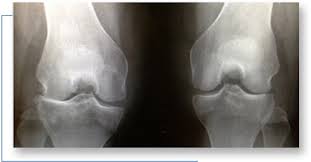

It is formed by shaping and preparing the bone cement with antibiotic. Total knee replacement (tkr, also called total knee arthroplasty) is one of the most successful procedures in the second surgery is to remove the spacer and insert a new prosthesis. Ogm knee spacers are basically composed of 2 separate parts.

Et al topical antibiotics and topical antimicrobial agents in acne therapy. Physical therapists are trained to diagnose and treat knee pain and to help ease your pain and res. When it comes to the knee and therapy it's good to get some answers on the anatomy of the knee and how that relates to physical therapy exercises for the. These knee spacers may be static or mobile spacers, with the latter presumably providing improved function for the patient and greater ease of surgical reimplantation.